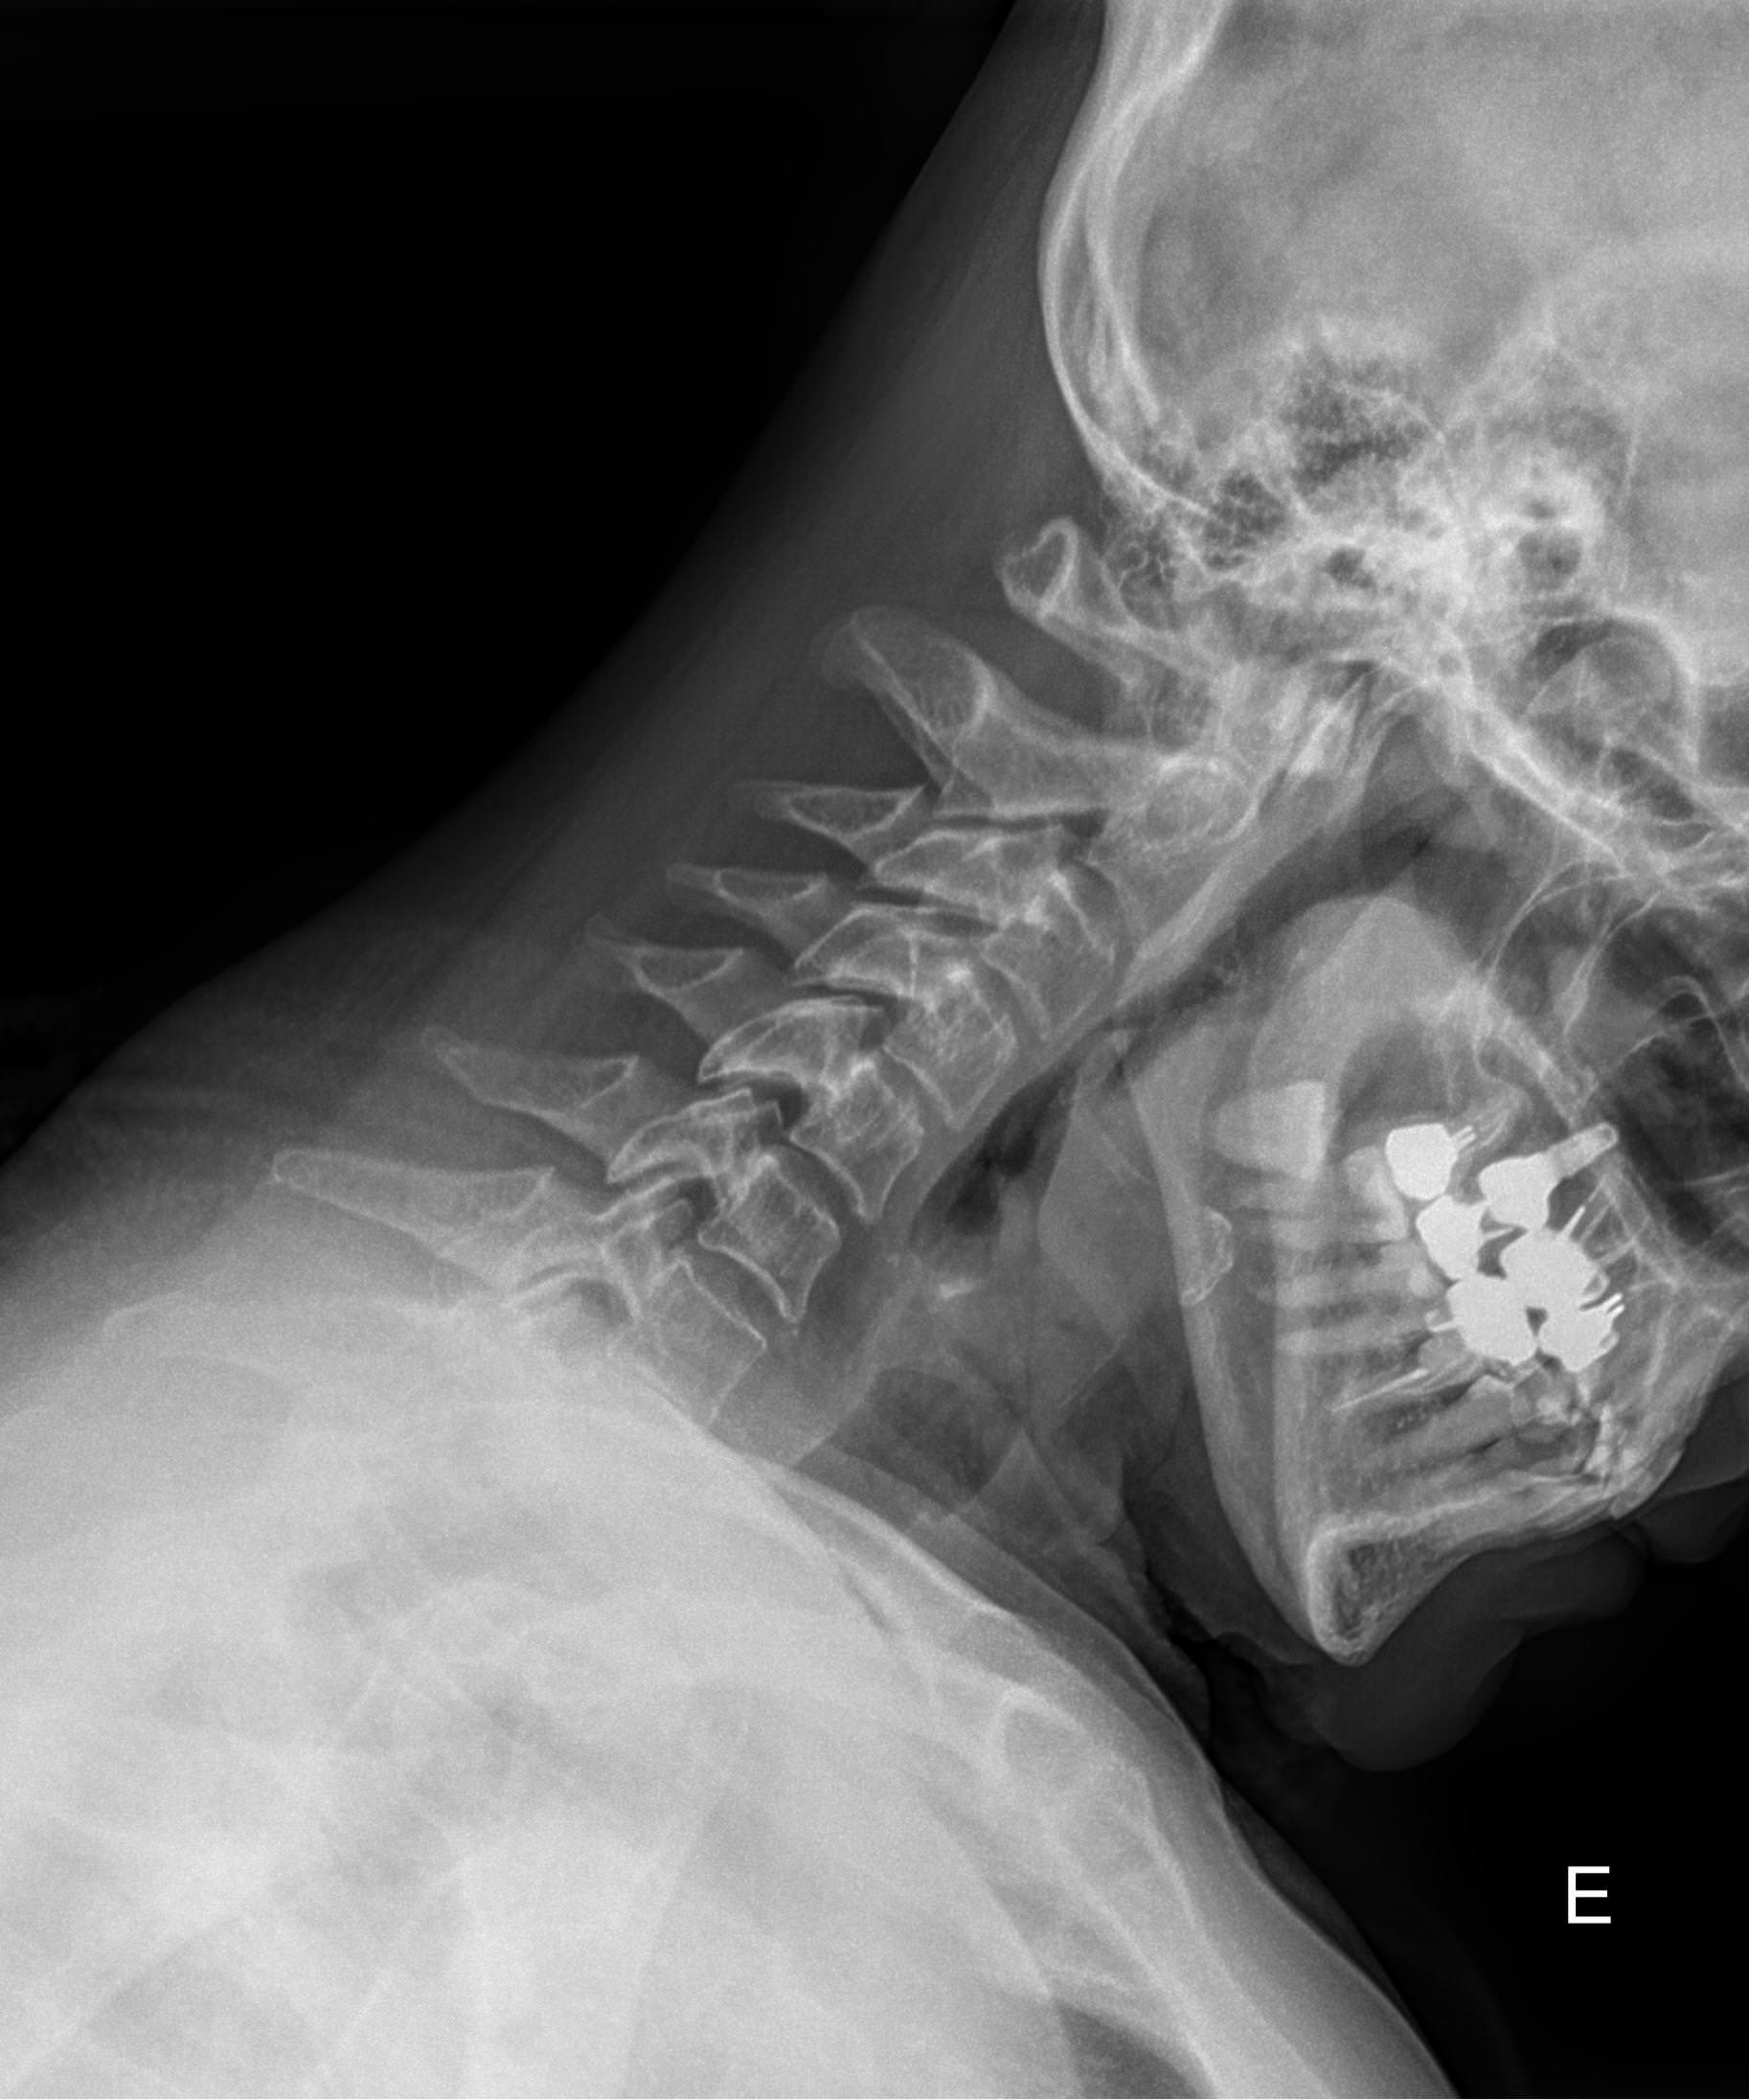

Процедура не требует специфической подготовки. Однако необходимо снять с шеи и головы все металлические предметы: украшения, съемные медицинские гаджеты и предупредить о несъемных. Затем надеть защитный фартук. Далее надо сесть или встать возле пластины детектора и прижать к ней голову, как покажет рентгенолаборант: носом и лбом, носом и подбородком или только подбородком, это зависит от того, какие пазухи подлежат съемке. Так как пазухи парные, то есть расположены симметрично, голову нужно держать ровно, не поворачивая и не отклоняя вправо или влево. Если будет указано в направлении, выполняется несколько снимков в разных проекциях, чтобы были видны разные пазухи.

Во время съемки по команде рентгенолога надо вдохнуть и не дышать, а также не шевелиться 1-2 секунды. Снимки можно получить на руки сразу, их описание ― в течение дня.